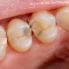

Diş Enfeksiyonlarıbakterilerin pulpa gibi oral dokulara nüfuz etmesiyle ortaya çıkar,periodontalcepler veya çevreleyen kemik. Bu bakteriler rastgele istilacılar değildir. Genellikle belirli koşullar altında fırsatçı hale gelen ağız mikrobiyomunun bir parçasıdırlar.

Son on yılda yapılan araştırmalar şunu vurguluyor:Diş Enfeksiyonlarıgenellikle polimikrobiyaldir. Bu, birden fazla bakteri türünün etkileşime girdiği, iletişim kurduğu ve bazen birbirini koruduğu anlamına gelir. Bu karmaşıklık, neden tek başına antibiyotiklerin tedavide her zaman merkezi çözüm olmadığını açıklıyor.Diş Enfeksiyonları.

Bir diğer kritik nokta ise yerelleştirmedir. BirçokDiş Enfeksiyonlarıbelirli bir alanla sınırlıdır. Bir enfeksiyon lokalize kaldığında, vücudun bağışıklık tepkisi ve mekanik diş müdahaleleri genellikle sistemik ilaçlardan daha büyük bir rol oynar. Bu, klinisyenlerin diş hekimliği bağlamında antibiyotiklerin gerekliliğini nasıl yorumladıklarını yeniden şekillendirdi.